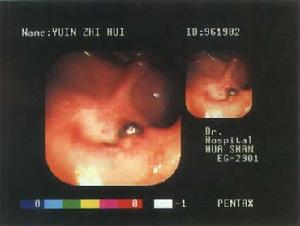

兒童消化性潰瘍確診2.內鏡檢查是確診潰瘍病、評定潰瘍活動程度、確定有無Hp感染及評價療效的最佳方法。

(1)根據部位分型:①胃潰瘍;②十二指腸潰瘍;③複合性潰瘍:胃和十二指腸潰瘍並存。

(2)根據內鏡所見分期:①活動期:潰瘍基底部有白色或灰白色厚苔,邊緣整齊,周圍黏膜充血、水腫,有時易出血;水腫消退,呈黏膜向潰瘍集中。十二指腸潰瘍有時表現為一片充血黏膜上散在小白苔形如霜斑,稱“霜斑樣潰瘍”。②癒合期:潰瘍變淺,周圍黏膜充血水腫消退,基底出現薄苔,薄苔是癒合期的標誌。③瘢痕期:潰瘍基底部白苔消失,遺下紅色瘢痕。以後紅色瘢痕轉為白色瘢痕,其四周黏膜輻射狀,表示潰瘍完全癒合,可遺留輕微凹陷。